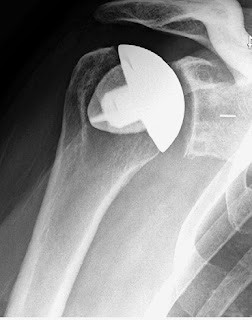

These authors report the minimum two year followup on 149 of 157 patients with glenohumeral arthritis from 14 different centers treated with a press-fit, porous-coated, metaphyseal fixed humeral implant between July 2011 and November 2012 in a U.S. Food and Drug Administration (FDA) Investigational Device Exemption (IDE)-approved protocol.

The mean age and sex-adjusted Constant, SST, and ASES scores improved from 56% preoperatively to 104% at two years (p < 0.0001), from 4 points preoperatively to 11 points at two years (p < 0.0001), and from 38 points preoperatively to 92 points at two years (p < 0.0001), respectively.

The mean forward elevation improved from 103° ± 27° to 147° ± 24° (p < 0.0001) and the mean external rotation, from 31° ± 20° to 56° ± 15° (p < 0.0001). The mean strength in elevation, as recorded with a dynamometer, improved from 12.5 to 15.7 lb (5.7 to 7.1 kg) (p < 0.0001), and the mean pain level, as measured with a visual analog scale, decreased from 5.9 to 0.5 (p < 0.0001).

There were three postoperative complications that resulted in revision surgery: infection, glenoid component loosening, and failure of a subscapularis repair. There was no evidence of migration, subsidence, osteolysis, or loosening of the humeral components or surviving glenoid components.

They point out that humeral complications in shoulders with stemmed humeral components are rare, but can include periprosthetic humeral fractures during and following total shoulder arthroplasty, proximal humeral bone loss due to stress shielding, humeral stem loosening, and osteolysis. They also point out that removal of a well-fixed humeral stem can be difficult and can result in additional destruction of proximal humeral bone. They assert that a stemless humeral component could provide a method for (1) making revision easier by preservation of the humeral bone and (2) improving anatomic positioning of the humeral head; however neither of these assertions is tested in this paper. It is not known whether this approach saves operating time or has a lower cost in comparison to standard humeral implants.

It is of note that the application of the the stemless implant was limited; it was used for less than 1/3 (31.4% (157)) of the 500 primary anatomic total shoulder arthroplasties performed by the study surgeons during the enrollment period. Reasons for non-use were many: low preoperative Constant score, diagnoses other than osteoarthritis or posttraumatic arthritis, patients with risk of falls, prior open surgery, cortisone use, physical activities that could affect the outcome of surgery, or lack of sufficient quality bone to seat and support implant (the surgeon attempted to compress the neck cut surface with his/her thumb; bone that was easily compressed with minimal force was considered insufficient for implantation of this device).

In contrast to this stemless device, we find that an impaction-grafted humeral component not only preserves but adds bone to the humerus, enables positioning of the humeral articular surface in the desired location (including an eccentric offset when needed as shown in this link) and is applicable to essentially the full range of shoulder arthroplasty indications, rather than being subject to the restrictions for a stemless prosthesis described in this article.